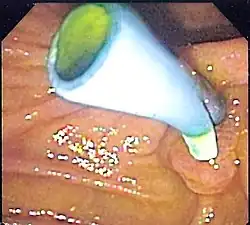

Stent do drenażu dróg żółciowych i drenażu trzustki zapewniają drenaż trzustki i żółci z pęcherzyka żółciowego, trzustki i dróg żółciowych do dwunastnicy np. we wstępującym zapaleniu dróg żółciowych w niedrożności z powodu kamieni żółciowych.